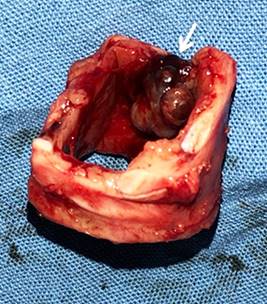

Masculino de 47 años, fumador, referido a nuestro centro hospitalario por la presencia de tumor intratraqueal con hemoptisis de 3 días seguidos de 500 ml/día, misma que cedió espontáneamente y de 15-20 eventos subsecuentes de 100 ml/día en los últimos seis meses. Estos eventos fueron manejados en otro centro hospitalario en donde se realizó tomografía torácica (Figura 1) y biopsia por broncoscopia flexible, con resultado patológico de tejido inflamatorio necrótico.

Figura 1: Tomografía computarizada de corte axial de pulmón, en donde se evidencia (flecha) tumor intratraqueal.